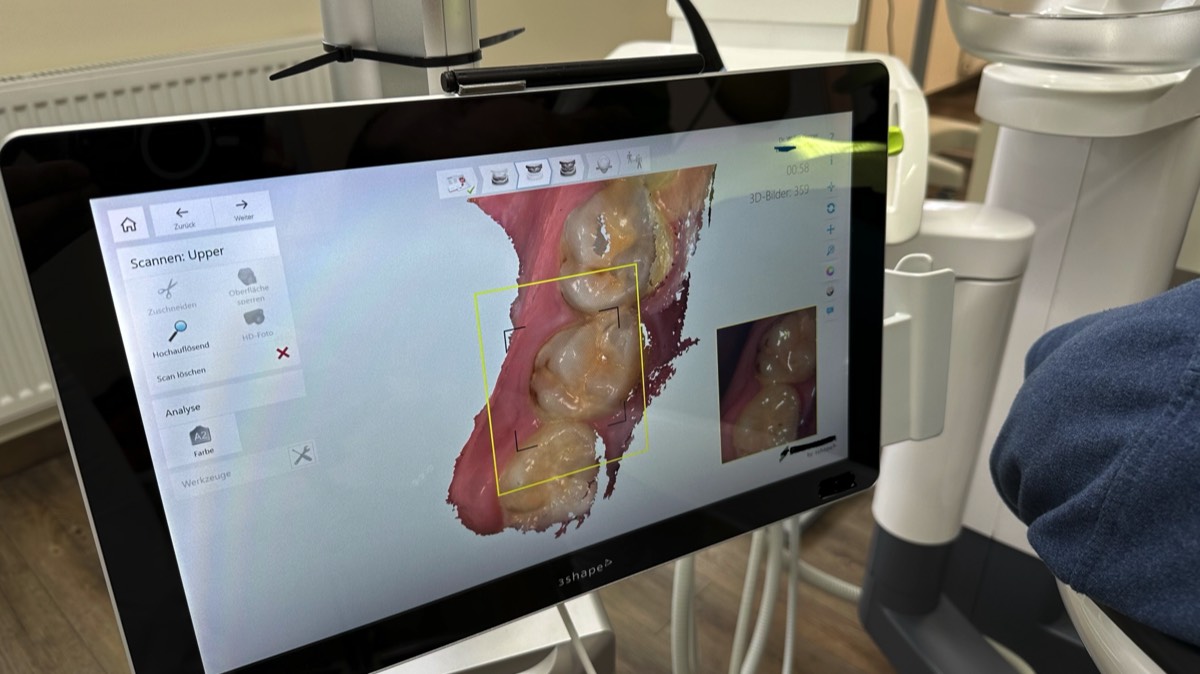

Digitale Abformung

Seit 2019 nutzen wir einen eigenen digitalen intraoral Scanner, mit dem wir die Zähne und Kiefer unserer Patienten dreidimensional aufnehmen können. Diese hoch präzisen Aufnahmen sind geeignet, um Kronen, Brücken (auch auf implantaten), sowie Prothesen und Schienen ohne einen konventionellen Abdruck herzustellen. Die unbeliebten Abdrücke mit Abdruckmaßen werden bei uns nur noch in Ausnahmefällen genommen.